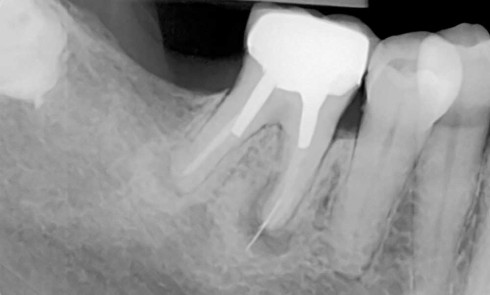

Les protocoles d’extraction-implantation immédiate, décrits pour la première fois en 1976 par Schulte et Heimke [1], se sont progressivement développés...